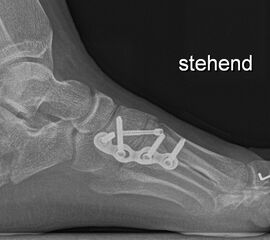

Calcaneus-Osteotomie

Die minimalinvasive Calcaneusverschiebeosteotomie bietet eindeutige Vorteile gegenüber dem offenen Verfahren, sodass wir bei Kindern und Jugendlichen nahezu keine offene Verschiebeosteotomie mehr durchführen. Am Calcaneus liegt die offene Wachstumsfuge dorsal. Bei der Durchführung müssen Schenkel der V-förmigen Osteotomie daher etwas steiler angelegt werden, in einem stumpfen Winkel (siehe Abb. 3 a-j). Für die Osteotomie liegen unsere Patienten auf dem Rücken und der BV wird für die exakte Seitaufnahme eingestellt. Der Fuß lagert auf einem hohen OP-Kissen und die Osteotomie kann bequem mit einem langen Kirschner-Draht und einem sterilen Stift angezeichnet werden (Abb. 15).

Abb. 16 a-f: Varisation einer valgischen Calcaneusstellung bei Knick-Senk-Fuß mit V-förmiger Osteotomie axiale Ansicht (a), seitliche Ansicht (b), d. p. Ansicht (c) und nach Entfernung der Drähte seitliche Ansicht (d), Caudalisierung des dorsalen Calcaneus bei iatrogenem Plattfuß nach Klumpfußüberkorrektur (e) und Cranialisierung beim Hohlfuß (f).